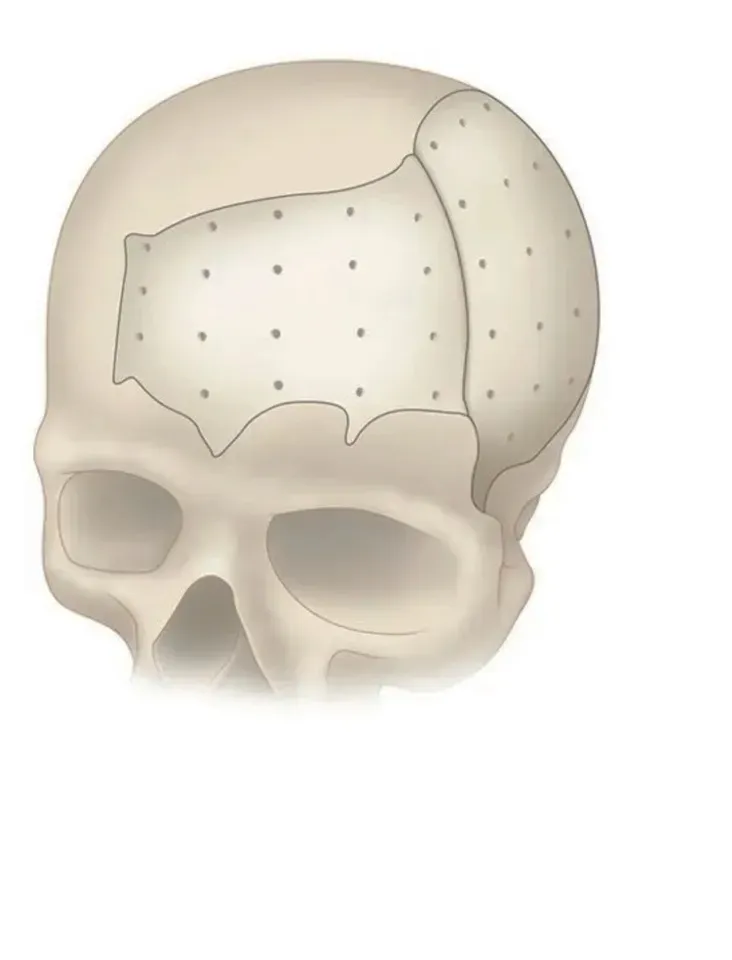

PEEK can be designed and provided in single or multiple pieces with just-fit or over-lay concept as indicated above. Additionally, this patient specific implant can be reliably fixated using cranial fixation systems.

Perfect Contour Reconstruction

Precisely match the natural contour and convenient to implant. CAD/CAM technology allows to restore the defect models and reconstruct the natural contour of the brain.